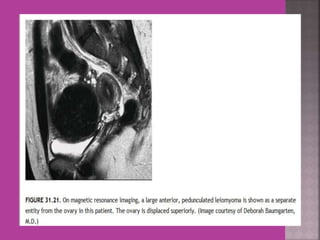

 Myoma—to differentiate myoma from

adenomyoma.localization of myoma—sub

serous/ intra mural or sub mucous.